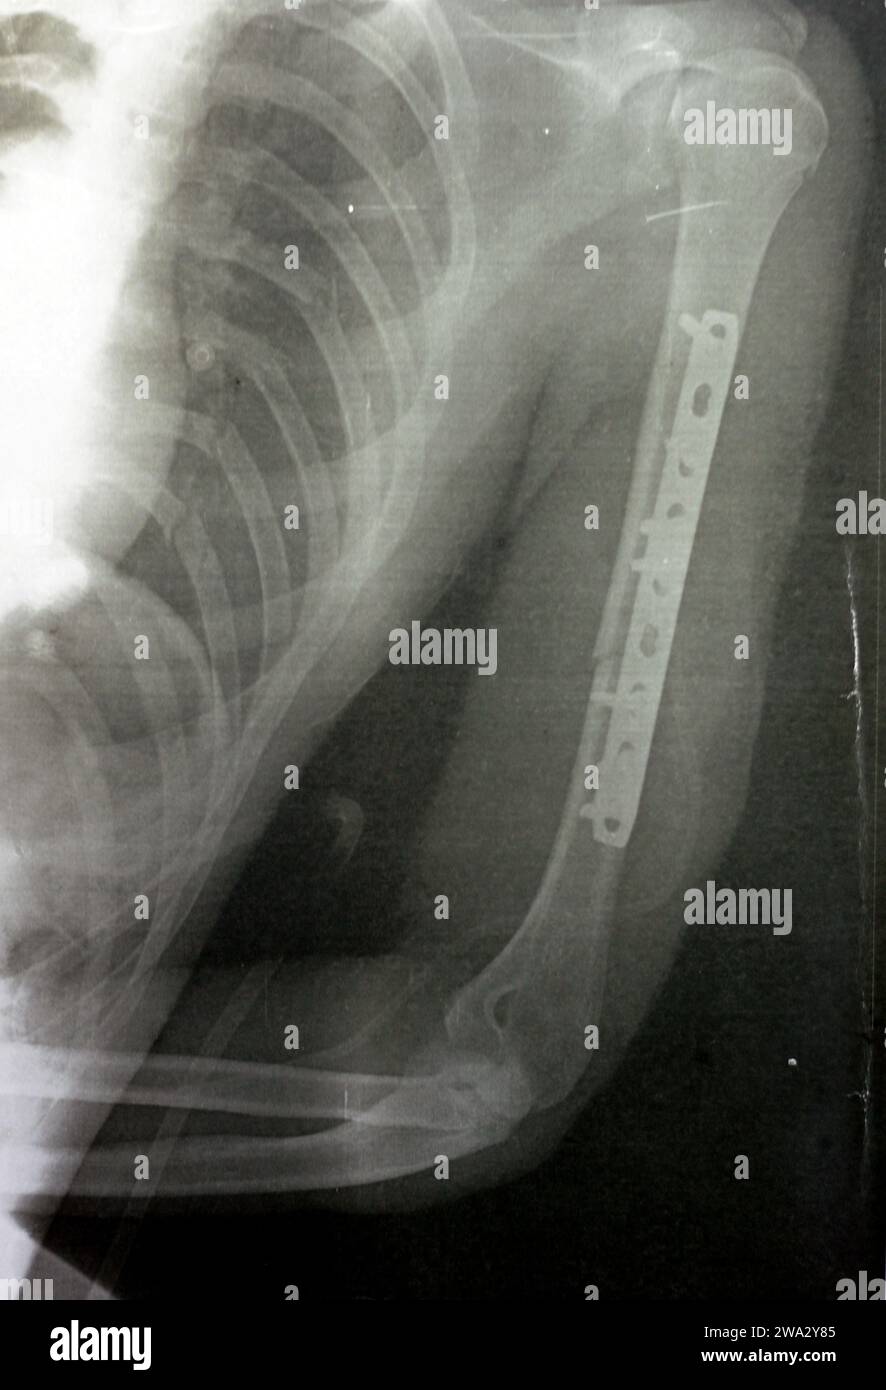

RF2WA30RC–Radiografia semplice che mostra frattura dell'omero sinistro dell'albero intermedio trasversale causata da un trauma diretto in un incidente stradale, gestito da riduzione aperta e fissa interna

RF2WA2Y85–Radiografia semplice che mostra frattura dell'omero sinistro dell'albero intermedio trasversale causata da un trauma diretto in un incidente stradale, gestito da riduzione aperta e fissa interna